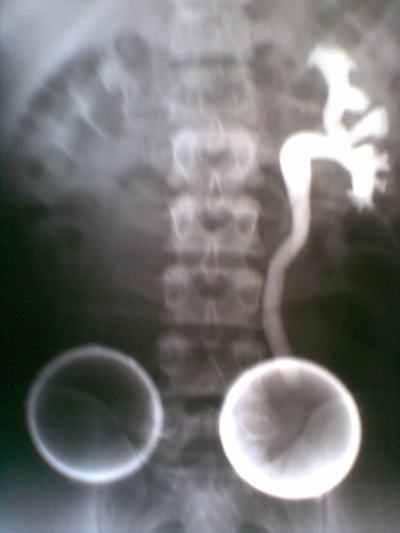

Kết quả siêu âm niệu qua thành bụng: thận phải có kích thước 6x8cm, thận trái bình thường. Tại cổ bàng quang có khối bề mặt nhắn, kích thước 6x5cm.

Kết quả UIV cho thấy trên phim 15 đến 180 phút thận trái bình thường (đường bài niệu giãn nhẹ do ép bóng tại niệu quản đoạn dưới), thận phải không ngấm thuốc cản quang. Bàng quang có khối choán chỗ (xin xem hình).